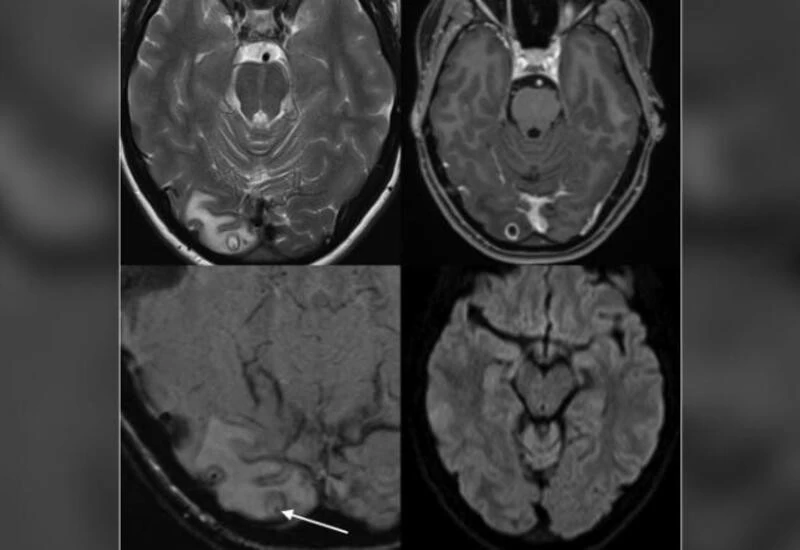

In these countries, NCC is usually diagnosed in immigrants or returning travelers who have spent time in endemic regions. Here, we report a case of NCC in a 25-year-old woman presenting with worsening visual symptoms in association with headache, diagnosed previously as a migraine with visual aura. This person had always lived in Australia and had never traveled overseas to a country endemic for T. solium.